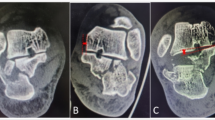

Records of participants with traumatic spine fractures were analyzed. Participants who had calcaneum fracture confirmed on radiographs were considered to have concomitant spine and calcaneum fracture. In these participants, variables noted were age, gender, mode of trauma, level and morphology of vertebral fracture and neurological status.

Concomitant calcaneum fracture was present in 43 participants out of a total of 358. The lumbar spine was involved in 72.09% of participants. 46.51% of participants had complete burst type of vertebral fractures. Neurology was found to be intact in 58.13% of participants. The association of concomitant calcaneum injury with the level of spine fracture and type of fracture were found to be statistically significant (pā<ā0.05). In particular, the association of concomitant calcaneal fracture with intact neurology and incomplete paraplegia (ASIA B, C or D) as compared to spinal injury cases without calcaneal fractures was statistically significant (pā<ā0.001).

Calcaneum fractures co-exist with spine fractures in 12.01% participants. Concomitant calcaneal fracture(s) with spine trauma indicate a greater chance of incomplete injury or intact neurology possibly due to dispersion of force vectors.